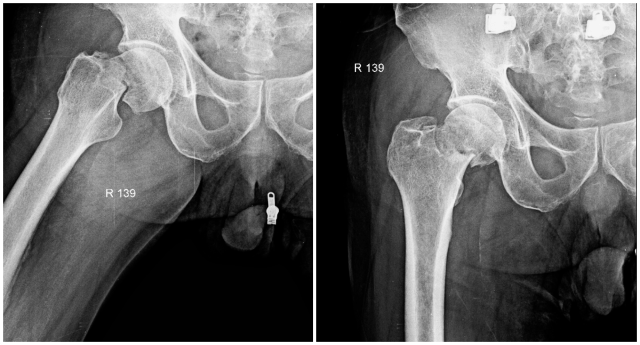

Frontal and frog leg lateral radiographs of the right hip. Transversely oriented right femoral neck fracture with one third shaft width lateral displacement and no intraarticular extension.